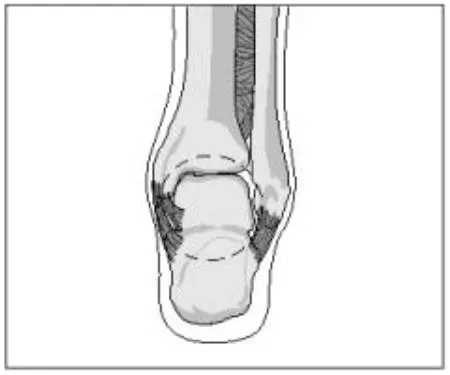

The ankle is a ring

Tibial plafond

Medial malleolus

Deltoid ligaments(medial lig.)

calcaneous

Lateral collateral ligaments

Lateral malleolus

Syndesmosis